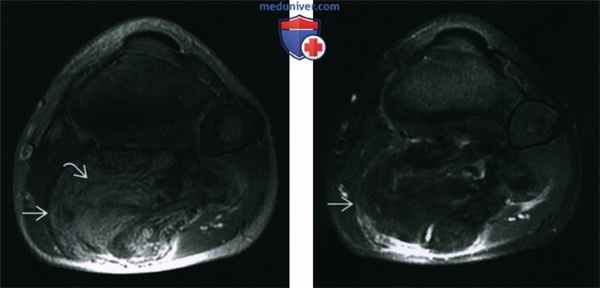

(Слева) MPT Т2ВИ в режиме подавления сигнала от жира, аксиальный срез: у этого же пациента определяется частичное подавление сигнала от жирового компонента объемного образования, как и от подкожной жировой клетчатки. Перегородки и узловые компоненты остаются изо-интенсивными по отношению к мышечной ткани.

(Справа) МРТ, постконтрастное Т1ВИ в режиме подавления сигнала от жира, аксиальный срез: контрастное усиление объемного образования по периферии и в виде неотчетливых центральных зон. Мягкотканные узловые компоненты и характер накопления образованием контраста у взрослого предполагали бы злокачественную жировую опухоль, но у ребенка эти признаки позволяют заподозрить липобластому (подтверждена гистологически).